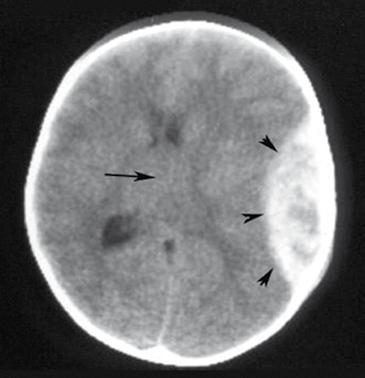

Polo is played by all age groups. Some of the middle-aged players already have some general medical risks or issues where thinning of the blood can apply. Some people use blood thinners after a long Welcome Night at a tournament to ease the hangover during the day. No clear statement exist for the use of blood thinners in contact sport.

For a hard blow against the head or a fall from the horse and resultant injury or fracture with the need for surgical treatment, blood thinners can be challenging and dangerous.

For several decades, low-dose aspirin has been widely prescribed for primary prevention of heart diseases such as heart attacks and strokes. Aspirin is also widely used by many people as a primary headache and flu medication. The reasoning behind the use of aspirin, is its property to block inflammation and irreversibly inhibit platelet function and the clotting of the blood. Simultaneously, however, aspirin increases the risk of bleeding, particularly in

the stomach or the bowels or following an accident. Hence, persons with a high-risk potential of bleeding – including a history of gastric or bowel bleeding or stomach problem, aged over 70 years, low platelet count in the blood, other accompanying diseases and concurrent use of non-steroidal anti-inflammatory drugs such as Ibuprofen or Advil – should be particularly careful in not taking aspirin unnecessarily. This holds true also for anyone involved in high-risk sports and who enjoy a fast polo chukka.

It is well known that aspirin is potentially beneficial in people with proven heart disease. For example, aspirin can be highly beneficial following a heart attack as it prevents further complications. However, in a normal and particularly heathy older population over 70 if aspirin is not indicated, it can be dangerous. Yet, inappropriate use of aspirin occurs in almost 30 percent of all persons taking the medication according to the American College of Cardiology and the American Heart Association.

Indeed, falling off a horse while taking aspirin and particularly combined with